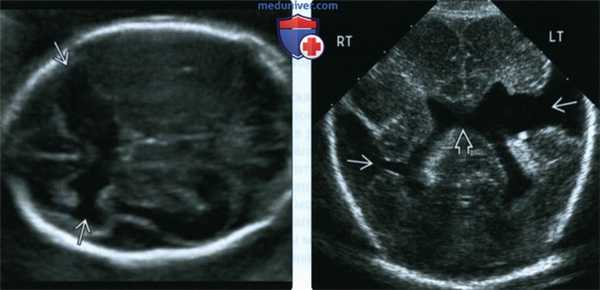

(Слева) При УЗИ в аксиальной плоскости у плода на 22-й неделе гестации видны двусторонние шизэнцефаличе-ские расщелины соединенные с передними частями боковых желудочков. Открытые дефекты чаще, чем закрытые, выявляются в пренатальном периоде.

(Справа) При УЗИ головки плода во фронтальной плоскости отмечаются отсутствие ППП и двусторонняя шизэнцефалия более выраженная слева. Шизэнцефалические дефекты расположены с двух сторон в 40% случаев.